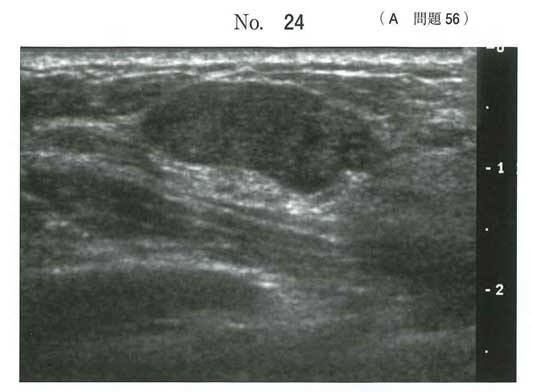

イヤーノートによれば、

線維腺腫は、20~30歳代に起こり、単発の腫瘤です。

年齢だけでも乳癌と乳腺症は切れます。